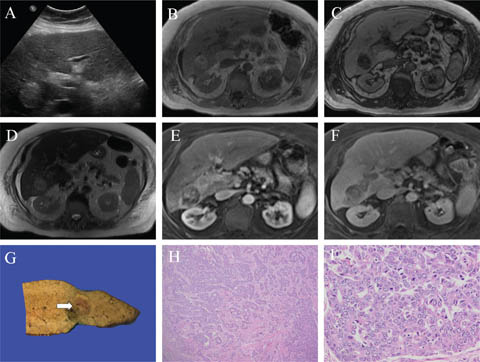

Fig 2

Figure 2. Representative images of hepatocellular adenoma. A and B. The large lesion (>5 cm) in segments 5 and 6 shows signal loss on the opposed phase T1 weighted image (B) compared to the in-phase T1 weighted image (A) denoting microscopic fat content. C. The lesion shows heterogeneous high signal on the T2 weighted image. D, E, and F. Following gadolinium administration, the lesion shows heterogeneous arterial (D) and portal phase (E) hyperenhancement and delayed phase washout (F). An ancillary finding of an enhancing capsule is depicted in (E) and (F). G. A partial hepatectomy from a separate patient shows a tan and poorly defined lesion grossly, with areas of hemorrhage and necrosis. H. Microscopically the neoplastic lesion (white arrow) shows an absence of portal tracts and is notably different from the background parenchyma (black arrow). I. Benign hepatocytes are arranged in cell plates up to two cells thick. Slides are stained with Hematoxylin and Eosin. Total image magnification: H - 25X; I - 400X.

Imaging features of HCA are often varied, with slightly different characteristics depending on the subtype. Hemorrhage with possible subsequent calcification, fat, and encapsulation may be seen. Of note, HCAs 5 cm or larger are at higher risk for both hemorrhage and malignant transformation into HCC, and require close imaging follow up. Males with HCAs are often treated by prophylactic surgical resection, particularly for solitary or large lesions, as a result of the increased incidence of the beta-catenin subtype.

Ultrasound is nonspecific, demonstrating a well-circumscribed lesion with variable echogenicity, more often hyperechoic. CEUS may increase specificity, particularly showing centripetal arterial flow, differentiating HCA from FNH, which typically illustrate a centrifugal arterial flow. Multiphasic contrast-enhanced CT demonstrates a well-circumscribed mass, which is typically isoattenuating on the unenhanced phase, with heterogeneous arterial phase hyperenhancement, usually returning to near isoattenuation on portal-venous phase and delayed phase imaging. Following hyperenhancement, contrast washout (hypoenhancement on the portal-venous and delayed phases) may be seen in both CT and MRI, mimicking malignant lesions.

On MRI, T1WI and T2WI signal intensities are variable, depending on the presence of fat, hemorrhage, and calcification. A high signal on fat-saturated T1WI denotes the presence of intratumoral hemorrhage. Contrast-enhanced phases are similar to CT, with early arterial enhancement, and are typically isointense on portal-venous phase imaging. HCAs are predominantly hypointense on hepatobiliary phase gadoxetic acid imaging, an important distinction from FNH. Opposed phase T1WI and fat-saturated T1WI are helpful to demonstrate microscopic fat and macroscopic fat, respectively, a characteristic feature of HNF1α-inactivated HCAs. Conversely, inflammatory HCAs have a characteristic high signal peripheral rim on T2WI, attributed to sinusoidal dilatation, termed the “atoll sign” (15).